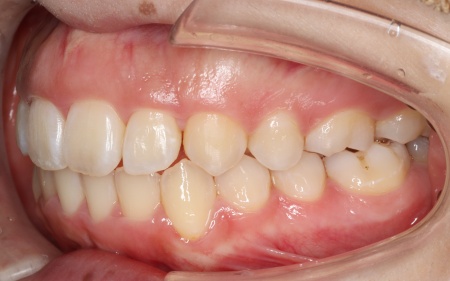

最後に、歯並びと噛み合わせがしっかりと整ったことを確認し、治療を終了しました。